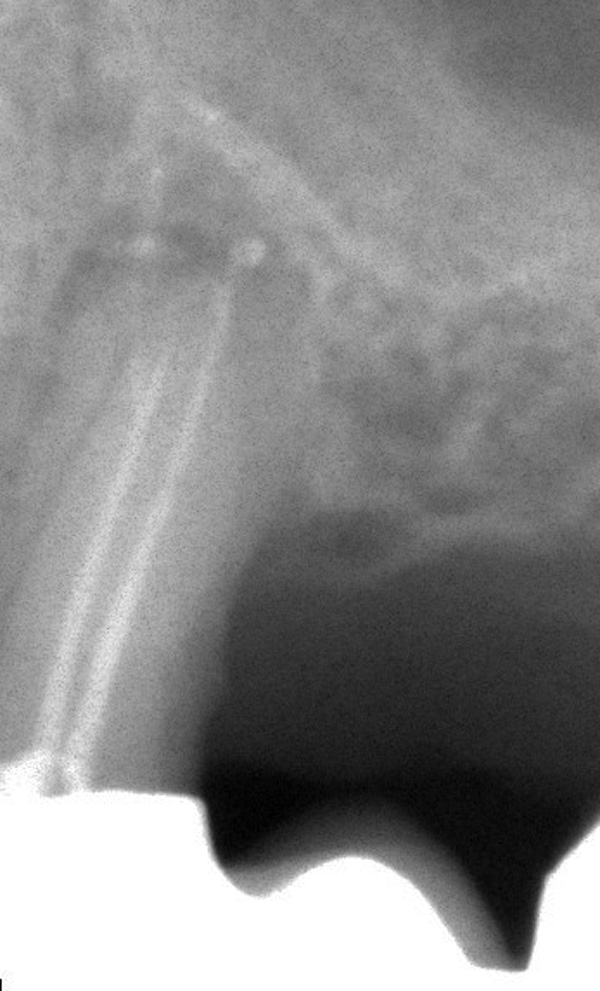

An Zahn 25 musste durch eine vorhandene, alte Brücke hindurch eine Wurzelkanalbehandlung gemacht werden. Gut sind die zwei Wurzelkanäle zu sehen und die Gabelung des einen Kanals im Bereich der Wurzelspitze (apikale Ramifikation).